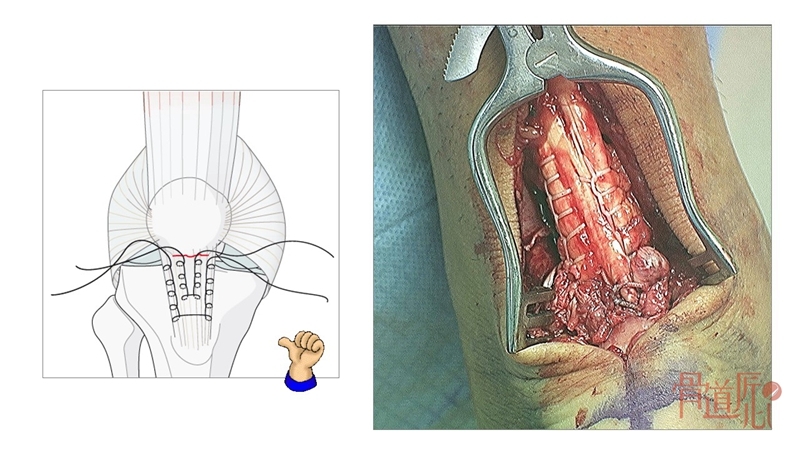

跟腱断裂修复技术中的金线